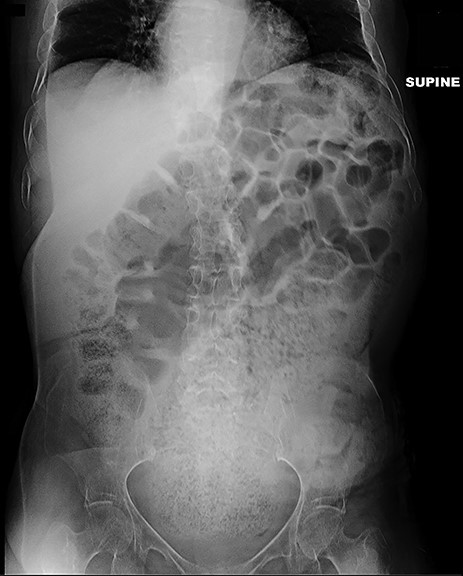

A 64-year-old female who resides in a nursing facility due to significant mental and physical disability presented to the emergency department with a 4-month history of chronic intermittent constipation. She had been treated multiple times for severe constipation and fecal impaction. On presentation, abdominal X-rays exhibited massive stool burden filling the rectum, which was distended cephalad to the diaphragm and anteriorly to the peritoneum occupying much of the abdominal cavity (Fig. 1). The patient was admitted to the hospital and aggressive bowel regimen was initiated with limited improvement. Given a history of multiple failed attempts with pharmacological therapy, surgical intervention was considered. A computed tomography scan of the abdomen showed a massive amount of stool in the rectosigmoid colon with no evidence of an obstructing lesion. The patient had undergone colonoscopy within 2 years of presentation with no evidence of polyps or malignant process. She was chronically malnourished, bedbound, non-communicative putting her at significant risk of morbidity with major intervention. Risks and benefits were discussed with the patient’s family, and it was opted for the least invasive surgical approach. We proceeded with creation of a loop colostomy of the descending colon through a mini left to midline 2.5 cm incision. The patient tolerated the procedure well. Post-operatively, she was treated with antegrade enemas through the distal limb of the colostomy as well as enemas and suppositories per rectum. Subsequent X-rays showed significant decrease in stool burden over the 14-Day period (Fig. 2). She was ultimately discharged to her nursing facility with normal bowel function.

Demonstrates massive megarectum secondary to large stool burden in context of chronic constipation.